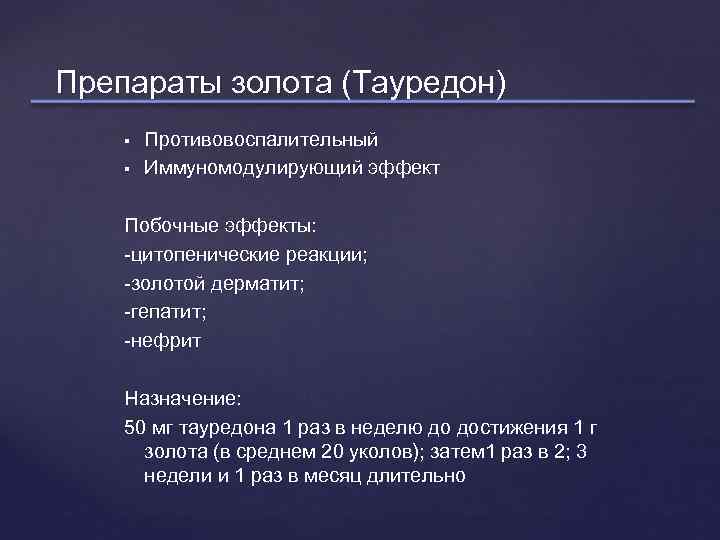

Препараты золота (Тауредон) Противовоспалительный Иммуномодулирующий эффект Побочные эффекты: -цитопенические реакции; -золотой дерматит; -гепатит; -нефрит Назначение: 50 мг тауредона 1 раз в неделю до достижения 1 г золота (в среднем 20 уколов); затем 1 раз в 2; 3 недели и 1 раз в месяц длительно

Препараты золота (Тауредон) Противовоспалительный Иммуномодулирующий эффект Побочные эффекты: -цитопенические реакции; -золотой дерматит; -гепатит; -нефрит Назначение: 50 мг тауредона 1 раз в неделю до достижения 1 г золота (в среднем 20 уколов); затем 1 раз в 2; 3 недели и 1 раз в месяц длительно